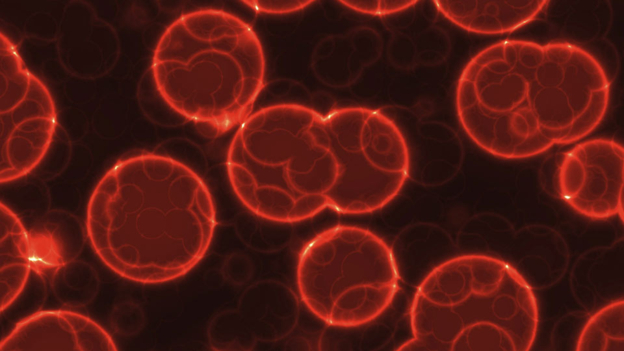

The team at Stony Brook University re-analysed existing cancer data and found that random cell mutation rarely gets to the point of causing cancer without some form of external factor like toxic chemicals or radiation.

Toxic chemicals in cigarettes and alcohol, and radiation from the sun make it more likely that random cell mutations result in cancer.